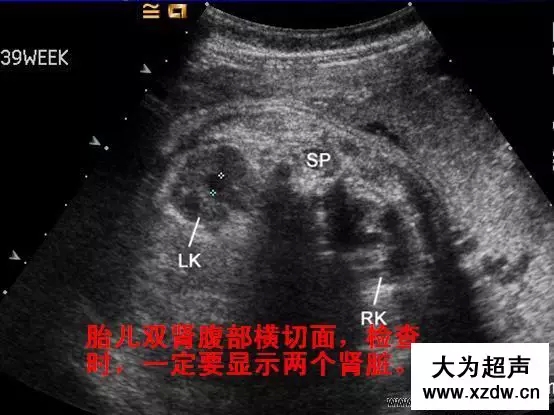

產(chǎn)科超聲正常圖片